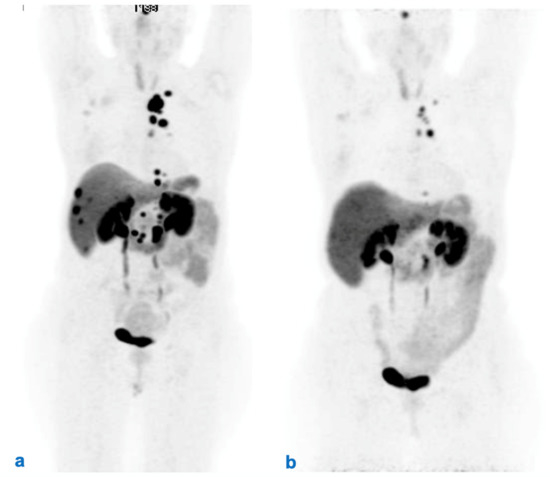

| 11. Follow-up after RLT | Follow-up should be patient-tailored and include morphological (CT and/or MRI) and/or functional (PET/CT with radiolabeled somatostatin analogs and/or FDG) imaging and biomarkers, chosen based on the characteristics of the tumor. The timing should be modulated based on prognostic parameters, while strongly considering safety issues. It is suggested to intercalate morphological and functional imaging to reduce the patient’s irradiation dose given the very long follow-up. |